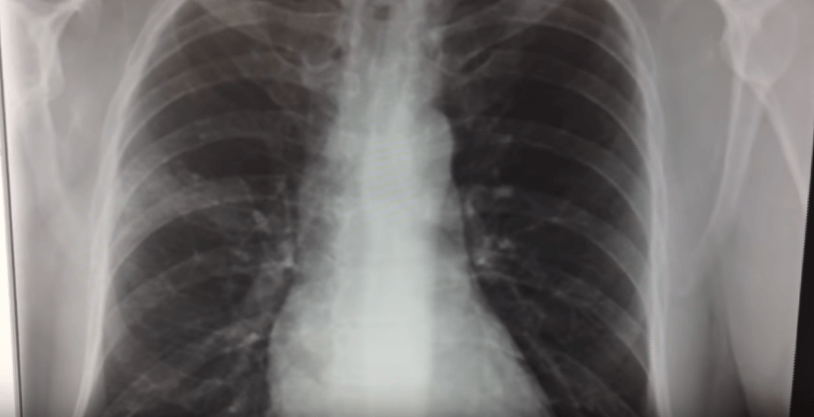

Confirmation requires a chest X-ray showing the characteristic features of pleural thickening and/or a cavity.